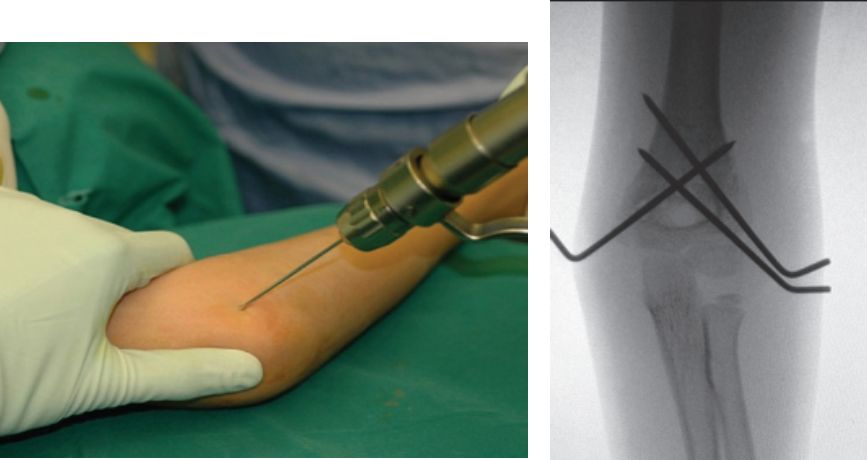

目前应用最多的当属儿童骨折的治疗。由于儿童骨骺的特殊性,克氏针具有对骨骺生长影响小、操作方便、可经皮置入等优点。

7、克氏针临时固定

克氏针不仅可以对骨块进行临时固定,达到良好的复位,为置入内植入物创造环境;也可以对内固定物进行临时固定,方便下一步操作。

8、克氏针长期固定

使用克氏针代替弹性髓内钉治疗小儿以及成人骨折,同样可以取得非常好的治疗效果。